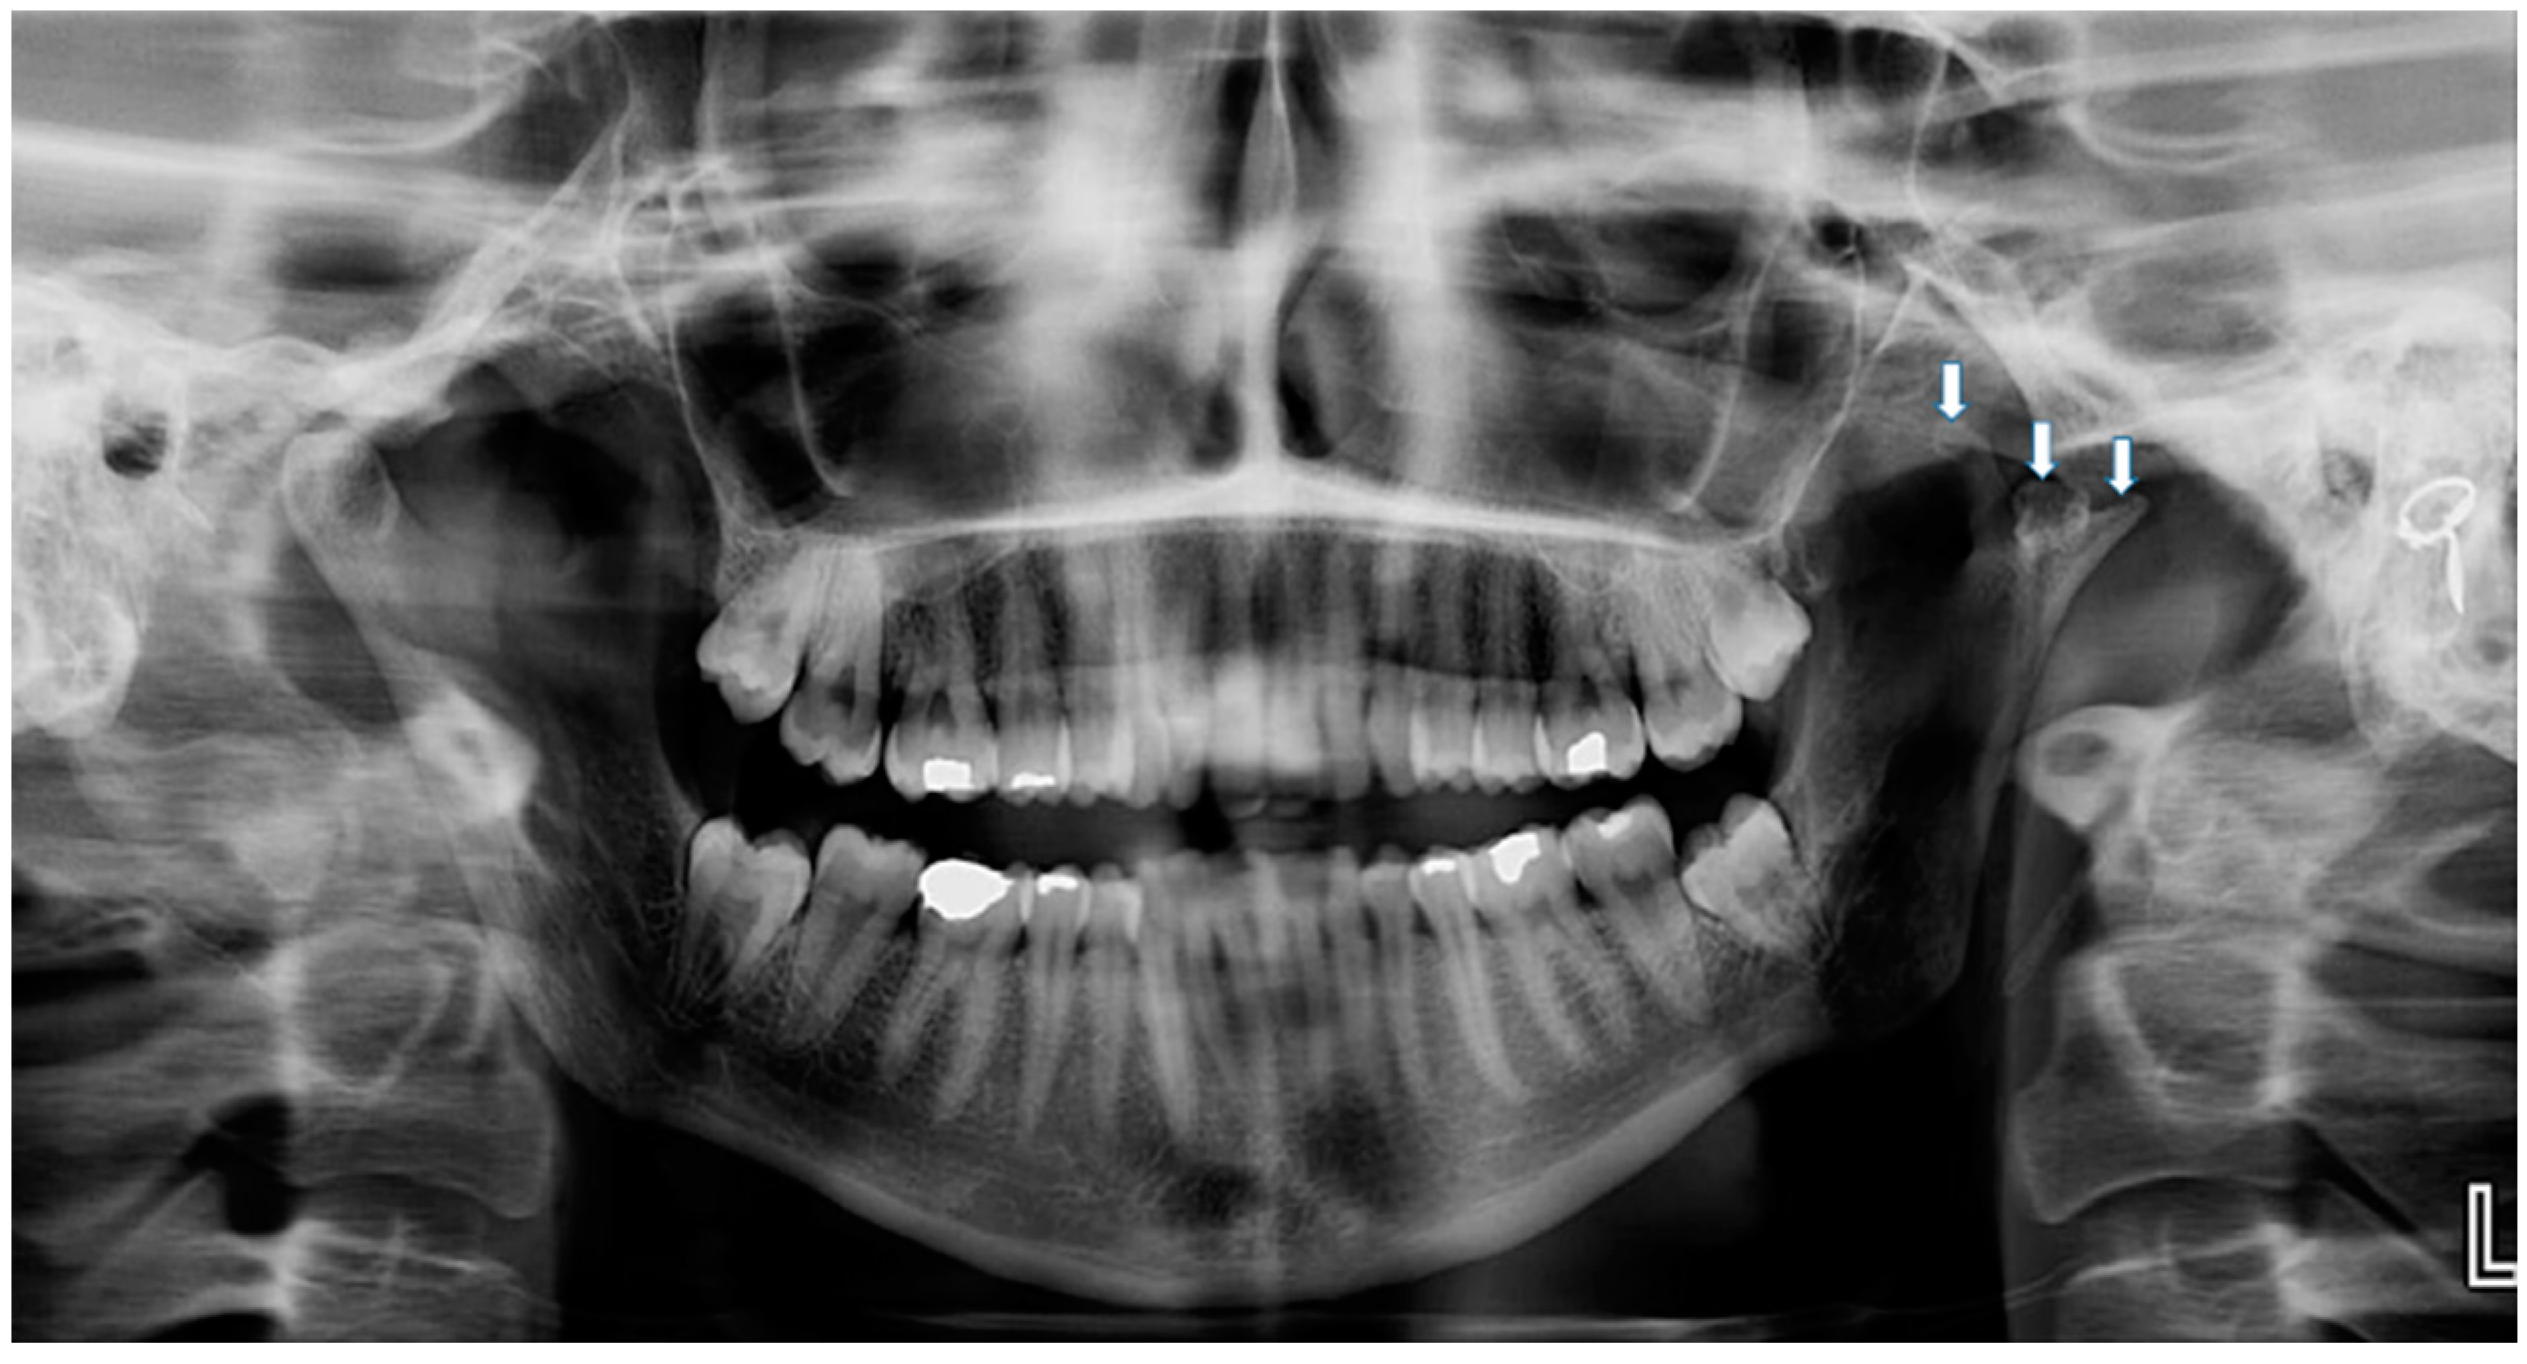

2. Case Report